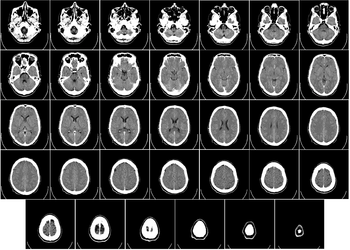

- ↑ From the National Library of Medicine's Visible Human Project. In this project, two human cadavers (from a man and a woman) were frozen and then sliced into thin sections, which were individually photographed and digitized. The slice here is taken from a small distance below the top of the brain, and shows the cerebral cortex (the convoluted cellular layer on the outside) and the underlying white matter, which consists of myelinated fiber tracts traveling to and from the cerebral cortex.